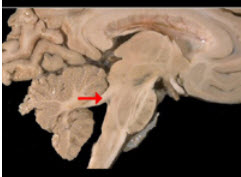

如图箭头所示为小脑哪个部位( )

A:小脑中脚

B:小脑下脚

C:小脑扁桃体

D:小脑上脚

E:小脑蚓部